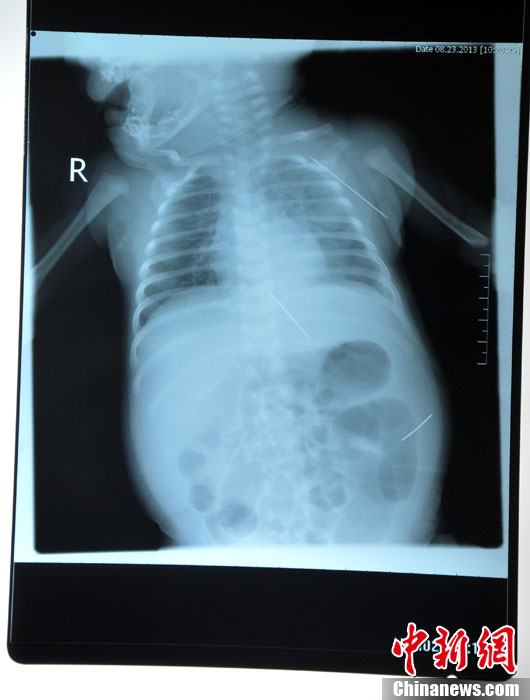

8月23日,黑龍江被“縫衣針”扎傷女嬰在哈爾濱醫科大學附屬第一醫院進行手術,成功取出三根長達4.5厘米的縫衣針,目前患兒正在術后觀察中,尚未脫離危險期。圖為三根鋼針在嬰兒體內的各個位置。(哈爾濱醫大一院供圖)中新社發